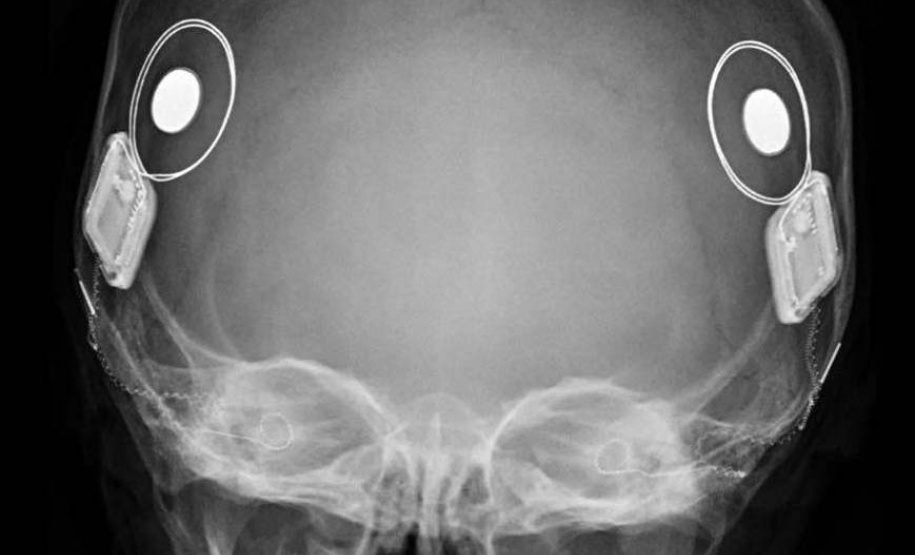

Conhecido popularmente como "ouvido biônico", o implante coclear é um dispositivo eletrônico de alta tecnologia inserido através de cirurgia. Diferente dos aparelhos auditivos convencionais, que apenas amplificam o som, o implante estimula diretamente o nervo auditivo.

O dispositivo conta com uma parte interna, que é colocada cirurgicamente dentro da cóclea (caracol da audição) e uma parte externa (que fica visível na parte posterior da cabeça) que é formada por um processador que capta o som ambiente. As duas partes são conectadas por um ímã, sendo que a externa deve ser retirada para tomar banho e dormir, e a bateria precisa ser carregada.